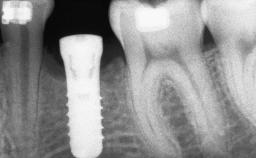

Ridge Preservation and Implant Placement for a Fixed Dental Prosthesis After a Car Accident

It is well known to clinicians that any removal of teeth will, over time, cause the dimensions of the alveolar ridge to be reduced by resorption of the bundle bone and by changes related to external modeling. This development is particularly evident in the crestal region with its thin buccal bone that consists of bundle bone almost entirely. The facial bone will rapidly resorb as blood supply from the periodontal ligament gets disrupted (Araújo and Lindhe 2005). There is no reason why traumatic tooth loss should not have the same consequences. It takes more than achieving implant osseointegration for a treatment outcome to be considered successful. No deficiency of bone or soft tissue is acceptable when an ideal esthetic outcome is the goal. Several articles (Sanz and coworkers 2011; Vignoletti and coworkers 2011) have reported on techniques of improving the alveolar ridge for implant treatment, notably focusing on protecting tissues from resorption.

Placement Protocol Early or late implant placement

Bone Volume Deficient vertically or deficient vertically AND horizontally